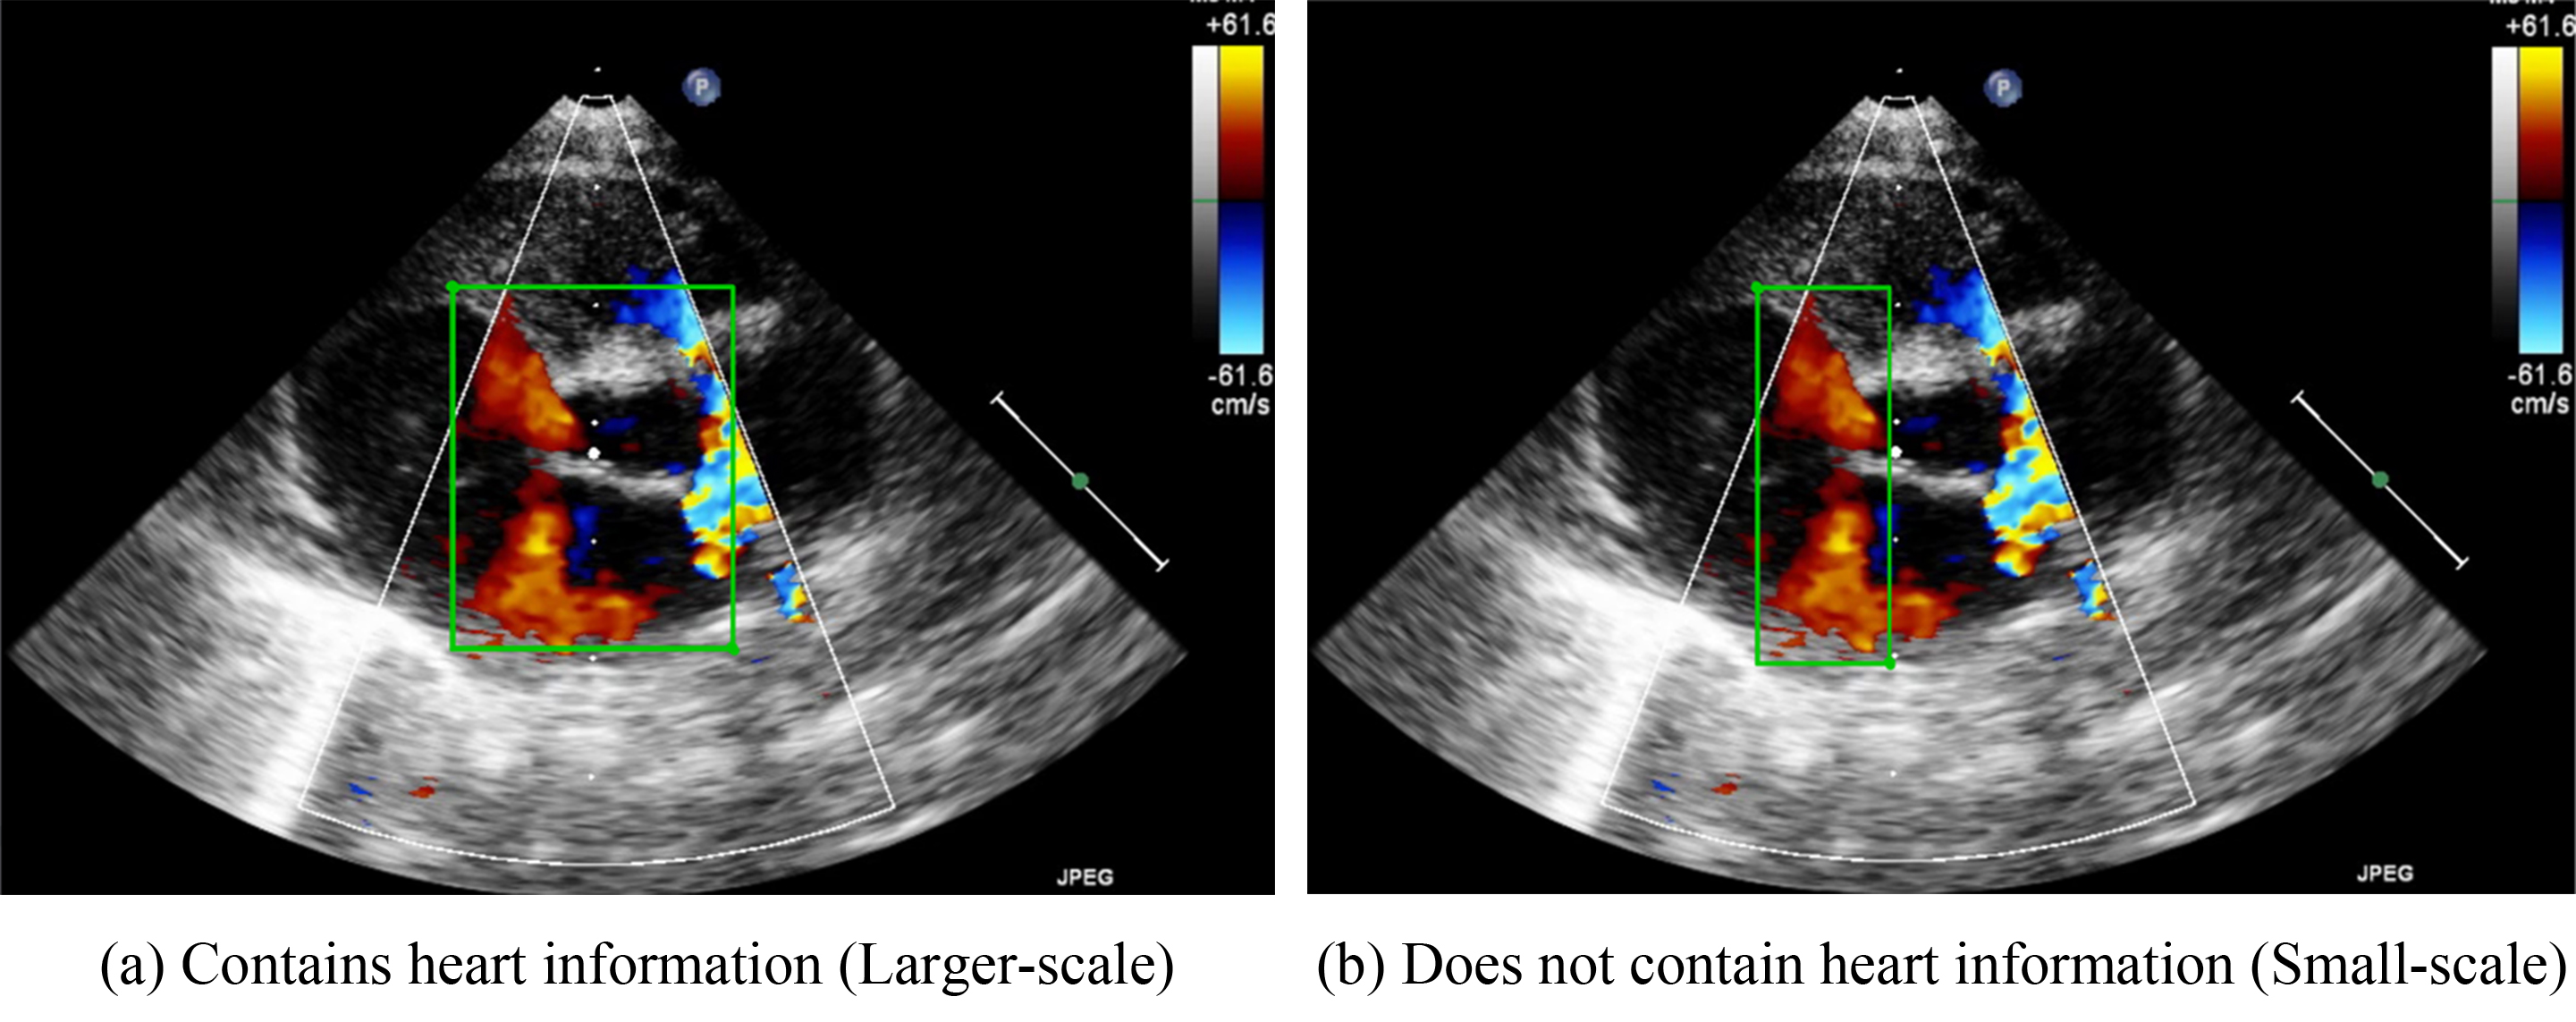

Because VSDs and ASDs require clear edges for detection, no standards for how these defects should be annotated have been developed. Therefore, the present study developed two methods for determining bounding box sizes for VSDs and ASDs. The first involves including the heart structure in echocardiographic figures. Fig. 3a, for example, presents the parasternal short-axis view of a heart. The bounding box includes the aorta in the center of the image. If an image is captured in the apical four chamber view, the bounding box should include the chamber septums. This standard was developed to ensure that the deep-learning algorithms would be able to consider the structure of the heart. Because the bounding box incorporates the heart structure, the size of the bounding box is larger. Therefore, in our study, we refer to this method as the large-scale bounding box method.

Fig. 3.

Schematic diagram of the marking ranges. (a) includes the heart structure of ventricular and atrium diaphragm. (b) only focuses on the jet area.

The other annotation method involves the color Doppler jet area. Fig. 3b depicts the narrow area in which diseases may be detected. Applying this method would enable doctors to focus on a specific region. Because the size of the bounding box is smaller when this method is employed, we refer to this method as the small-scale bounding box method.